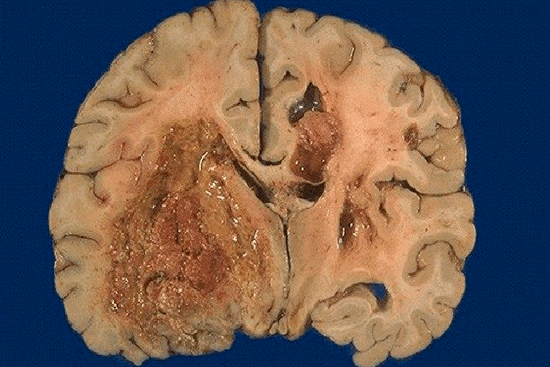

Глиобластома (ГБЛ) представляет собой образование гетерогенного строения с наличием больших зон некроза и васкуляризированной стромы, окруженное отеком. При микроскопическом исследовании не выявляется четкого края между опухолью и нормальным мозговым веществом [2]. Для ГБЛ характерна резко выраженная атипия клеток, их высокая митотическая активность, нередко наблюдаются внутриопухолевые кровоизлияния [2]. Несмотря на значительные усилия в уходе за пациентами, прогноз ГБЛ остается с медианной выживаемостью 12-14 месяцев и пятилетней выживаемостью менее 3 % [3].